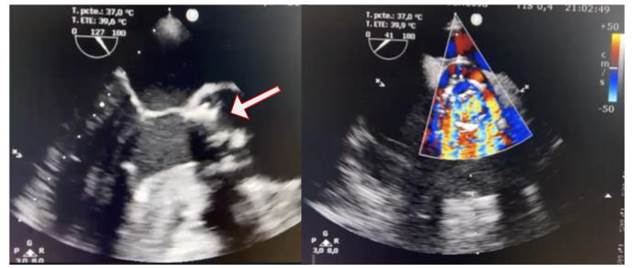

Se realiza un ecocardiograma transtorácico Doppler color, en el que se observa hipertrofia excéntrica del ventrículo izquierdo, función sistólica conservada, bioprótesis en posición aórtica estable, se registra una insuficiencia central con un tiempo de hemipresión (PHT) de 150 ms. Se produce un engrosamiento valvular con imagen móvil adherida a esta, con aumento de los gradientes 78/38 mmHg. Posteriormente, se realiza un ecocardiograma transesofágico Doppler color (Figura 3), que evidenció prótesis biológica en posición aórtica disfuncionante, con múltiples vegetaciones adheridas, la más grande de 8 mm por 5 mm, lo que genera destrucción del aparato valvular e insuficiencia severa (PHT 150 ms).

Figura 3 Ecocardiograma basal A. Transesofágico a 120 grados, se observan múltiples vegetaciones adheridas a bioprótesis aórtica, la más grande 8 mm por 5 mm (flecha). B. Doppler color a 45 grados, se observa jet de insuficiencia aórtica severa.